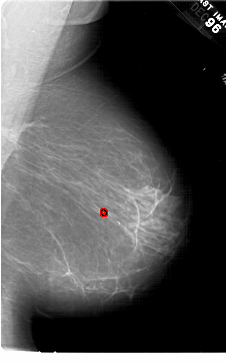

FILE: A_1452_1.RIGHT_CC.OVERLAY

TOTAL_ABNORMALITIES 1

ABNORMALITY 1

LESION_TYPE CALCIFICATION TYPE PLEOMORPHIC DISTRIBUTION CLUSTERED

ASSESSMENT 4

SUBTLETY 4

PATHOLOGY BENIGN

TOTAL_OUTLINES 1

BOUNDARY